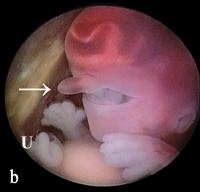

Triploider Embryo

Abbildung 6a-b: Vorderansicht (a) und Seitenansicht (b) eines triploiden (69,XXY) Embryos mit einer SSL von 21 mm. Eine einzige Orbita enthält 2 Augen (Synophthalmie). Es ist eine Rüsselnase vorhanden (Pfeil), die sich oberhalb des Medianauges befindet. Darmschlingen finden sich im proximalen Abschnitt der Nabelschnur (U) (physiologischer Nabelbruch).